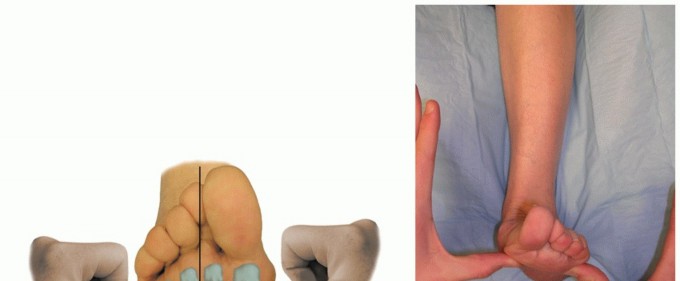

Figure 1: Reconstruction of the spring ligament using a peroneus longus autograft tendon transfer. Lateral view demonstrating the calcaneal bone tunnel reconstruction.

Figure 2: Anteroposterior view demonstrating the tibial bone tunnel reconstruction for spring ligament augmentation.

Figure 3: Lateral view detailing the tibial bone tunnel reconstruction trajectory.